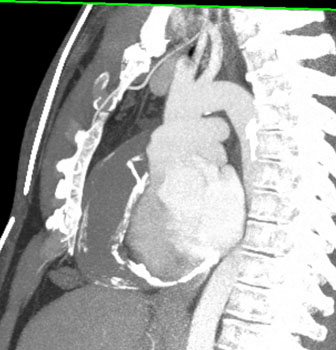

Question 5: 47 year old male with mass discovered on CT during chest pain workup. What is the diagnosis?

Diagnosis: Pericardial cyst

• Usually an incidental finding

• May be confused with a Morgagni hernia or duplication cyst or occassionally a thymic cyst

• Usually at right anterior costophrenic angle

• Water density on CT

• 2-30 cm in size

• Homogeneous without any enhancement